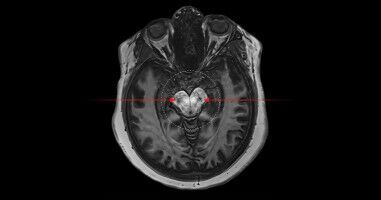

Health - Life Sciences - 13.11.2025

In every functional MRI scan, after the whir and pounding begins, there is a brief 10 to 20 seconds of stabilization as the machine's magnetic field settles into place. For decades, scientists have treated this period as dead time, discarding the data or 'dummy scans'. But a team of researchers at Western 's Centre for Functional and Metabolic Mapping (CFMM) have discovered these early few seconds offer some of the richest data a scanner can produce.